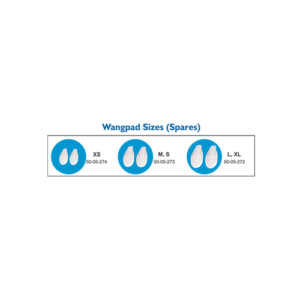

50-05-272/ 273, 274

Soft, skin-friendly cannula pad designed to enhance patient comfort and reduce skin irritation while using nasal cannula.